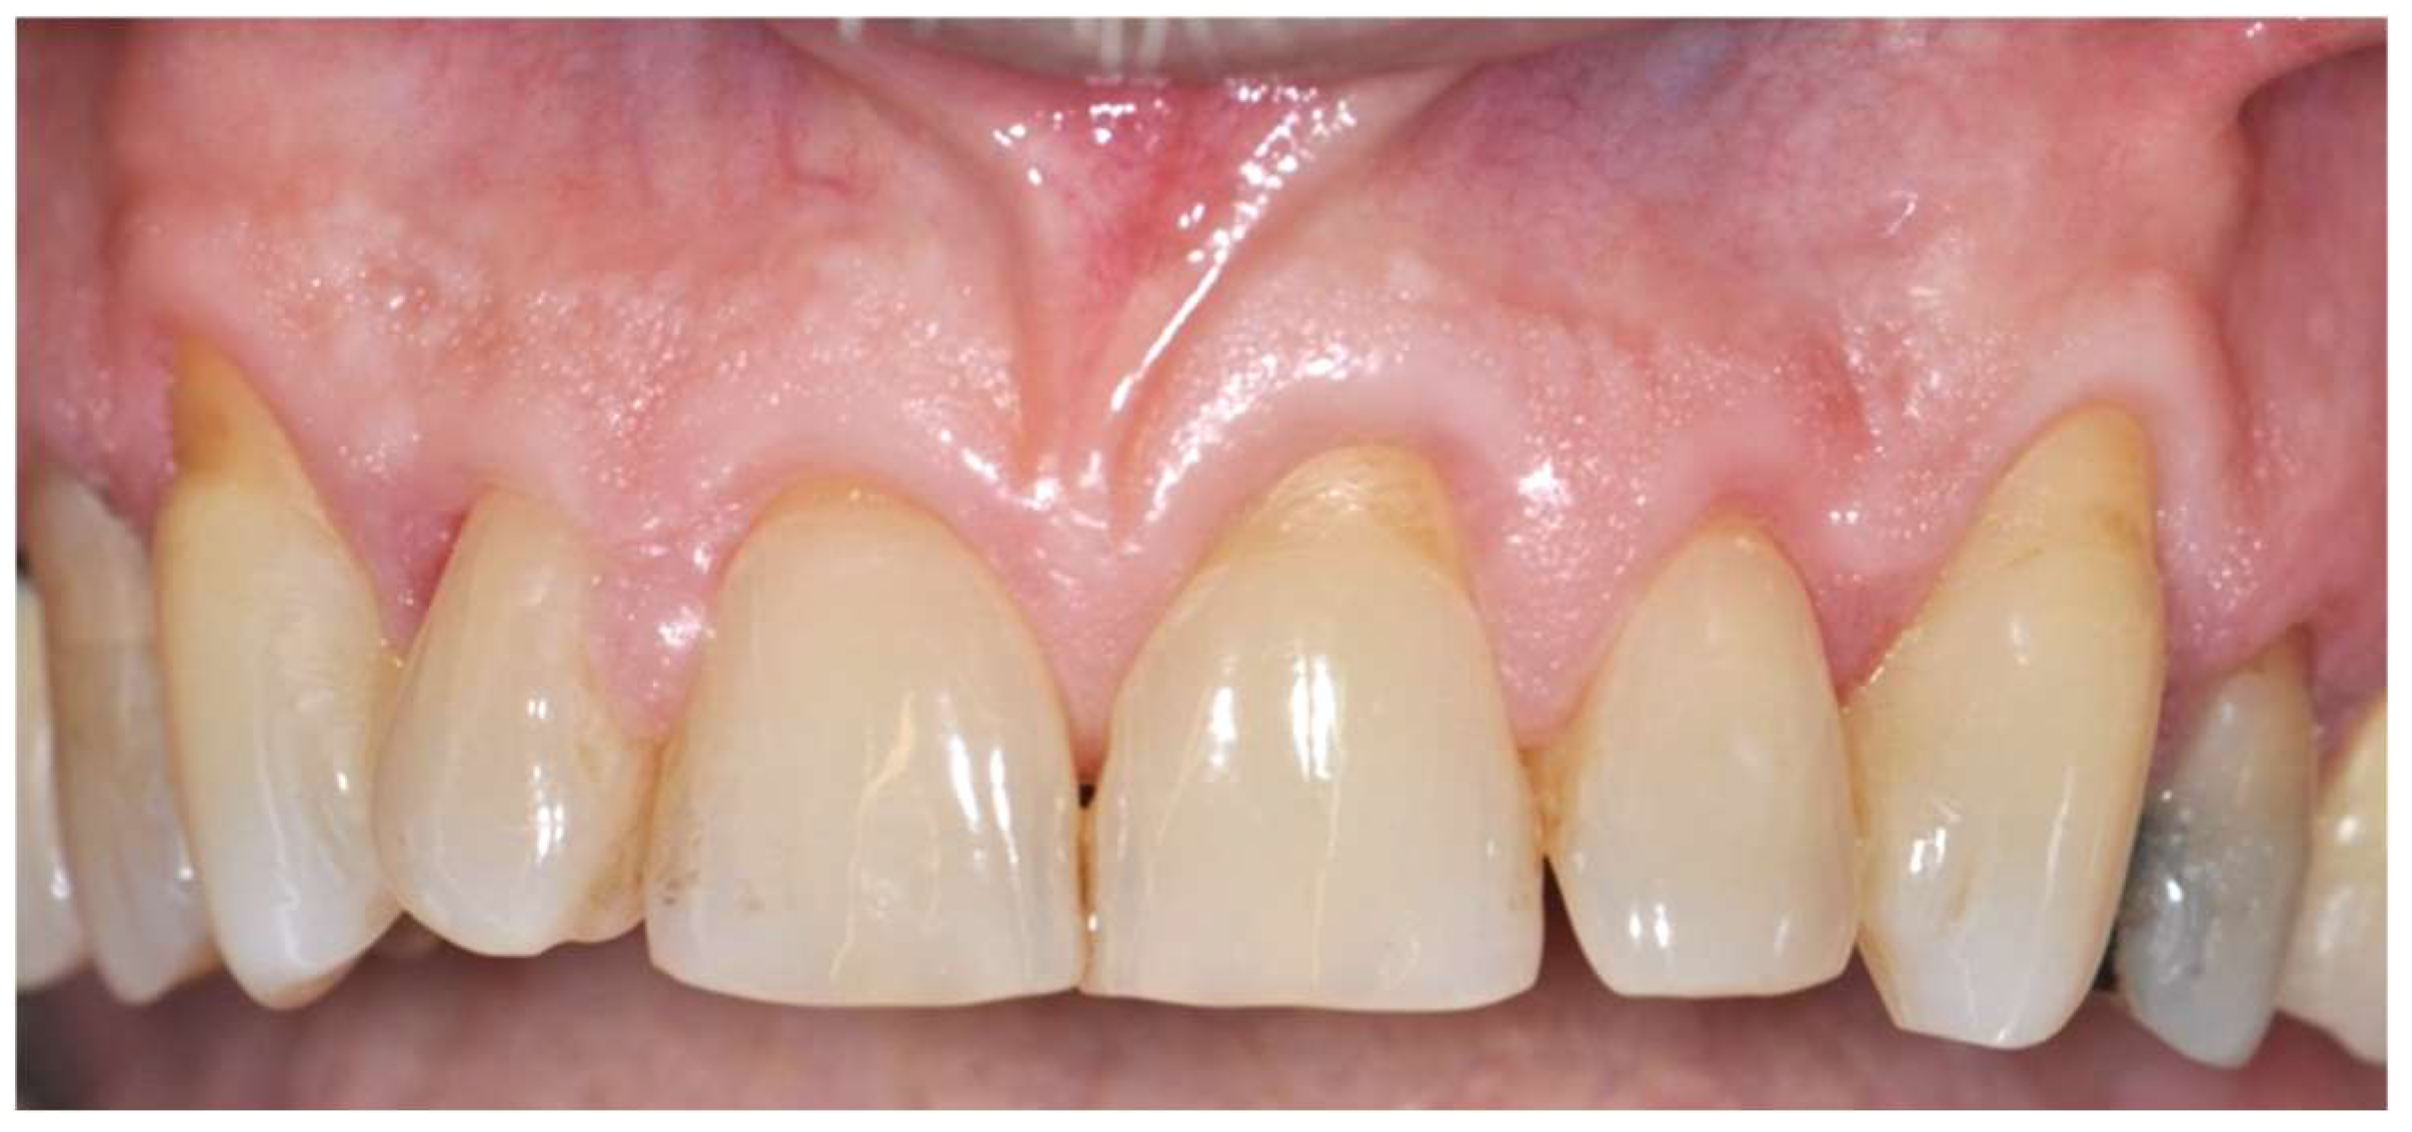

2. Case Presentation

2.1. Surgical Procedure